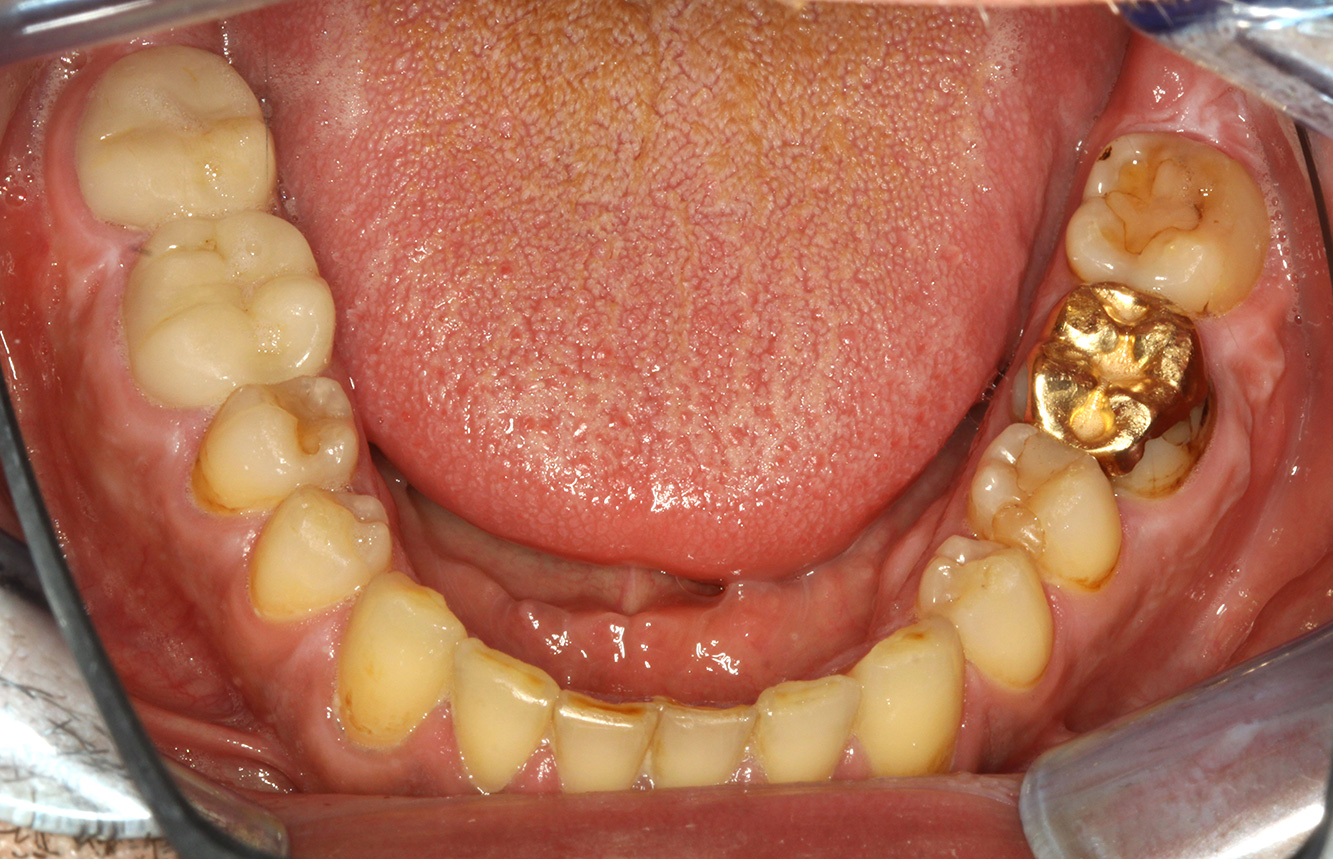

The patient is 39 years old and has previously undergone aortic valve replacement due to valve failure and endocarditis. ASS 100 is taken regularly as an anticoagulant. In terms of lifestyle, the patient’s diet is classified as caries-promoting due to the regular consumption of sugary foods and the fact that six to seven meals are consumed daily. The patient’s oral health indicates a moderate risk of caries, with active lesions. The risk of periodontitis is low, but gingivitis is present. The following recommendations are made for prophylactic treatment.

No specific instrument recommendations can be determined for the prophylaxis session. Targeted application of air and rotary polishing can be used to gently reduce plaque and stains on the restoration edges, and to reduce recolonization niches for cariogenic bacteria (19).

Fluoridation is recommended to further support the prevention of caries, and especially to prevent new formation around thethe restoration edges, and to seal the root surfaces. Both of these measures can reduce the teeth’s sensitivity to temperature.